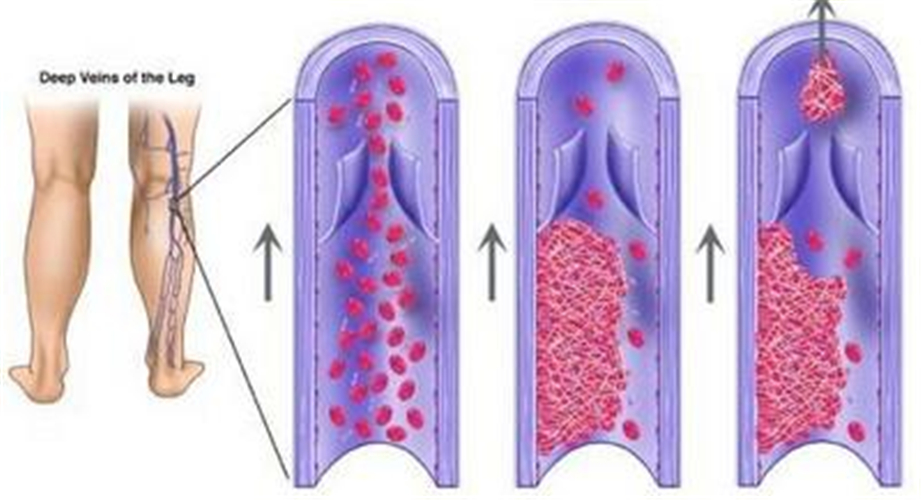

左小腿血栓性靜脈炎

血栓性靜脈炎症狀

血栓性靜脈炎高清

血栓性靜脈炎

A:所謂的遊走性靜脈炎簡單說就是在身體各處反覆發作的淺靜脈炎,主要表現為沿血管走行的疼痛感,局部出現紅色的線性或者網狀的索狀物,這些索狀物即是靜脈血管,觸摸著比較硬,有觸痛壓痛感,這些症狀可在身體各處交替出現,每次發病約持續1-2周的時間。遊走……

A:靜脈炎是靜脈的一種無菌性炎症,主要是由於血管損傷、藥物刺激、血栓等原因導致的血管通透性改變。表現為局部肢體腫脹、迴流受限、疼痛不適。個別患者可以看到沿著血管走形的紅色條索影、觸摸起來血管彈性減退,變硬。血栓性靜脈炎的患者,具體肢體出現皮膚髮……